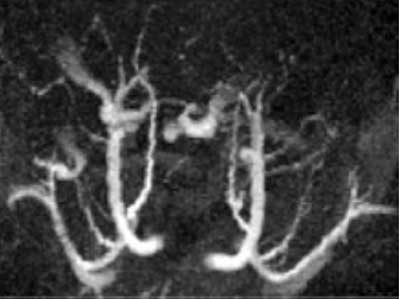

Animal: Rat

Sequence: FLASH-3D, TR/TE = 15/3 ms, Voxel Size = 300µm × 300µm × 1mm